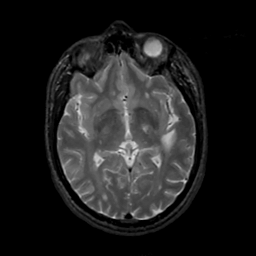

MR Study #3, February 24, 1991 -- Slice #24